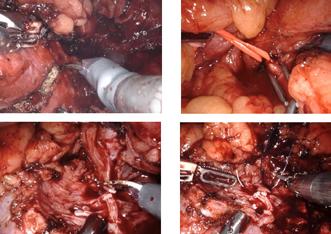

Chirurgia robotică în România

Prof. Univ. Dr. Nicolae Crișan, Asist. Univ. Dr. Maximilian Buzoianu